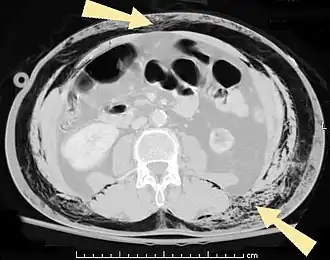

![]() КТ брюшной полости пациента с подкожной эмфиземой (указано стрелками) | |

Подко́жная эмфизе́ма — скопление воздуха в подкожной клетчатке грудной стенки, распространяющееся на другие области тела. Является симптомом повреждения лёгкого или воздухоносных путей[1].

В результате анатомической особенности клетчатки — отсутствия фасций — воздух довольно быстро распространяется на грудную клетку, шею, лицо, а также вниз на живот до мошонки (у мужчин) и бёдер[2].